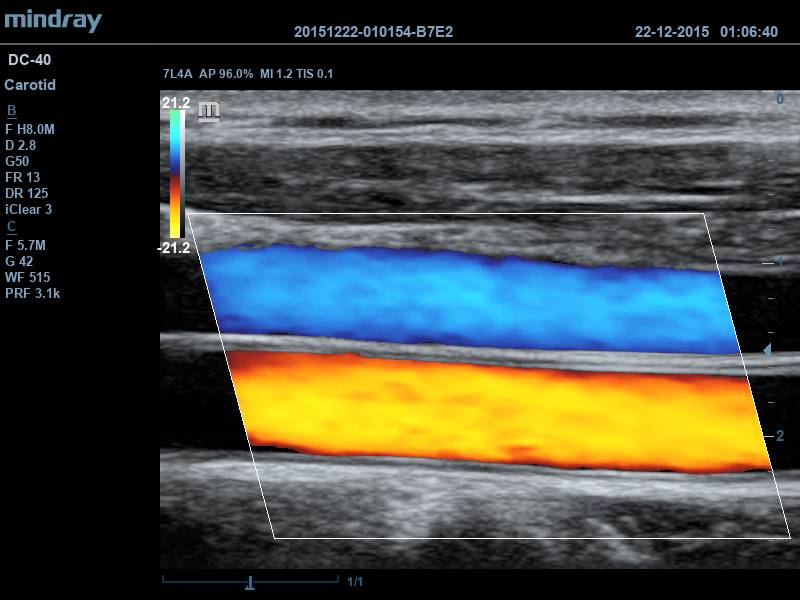

Ультразвуковая система среднего/высокого класса Mindray DC-45

Стационарный ультразвуковой диагностический аппарат Mindray DC-45 представляет собой значительно усовершенствованную модель аппарата Mindray DC-40. Основное отличие DC-45 от своего предшественника заключается в значительном увеличении размеров и разрешающей способности мониторов, а также применении более продвинутого ПО и поддержке объёмного внутриполостного датчика.

Новейшая серия УЗИ сканеров компании Mindray DC-40, DC-45, DC-40 Pro и DC-40 Exp зарегистрирована в России 5 февраля 2018 г. Аппараты этой серии имеют широкий выбор датчиков и функций, а также содержат ЖК монитор 15, 17, 19 и 21 дюймов, поворотную и регулируемую по высоте панель управления с встроенным сенсорным экраном 10,4”, угол наклона которого можно регулировать.

• Программное обеспечение для автоматического измерения толщины комплекса интима-медиа Программное обеспечение для оценки эластичности ткани методом компрессионной эластографии(поддерживается на датчиках 7L4A, L12-3E and L14-6NE)